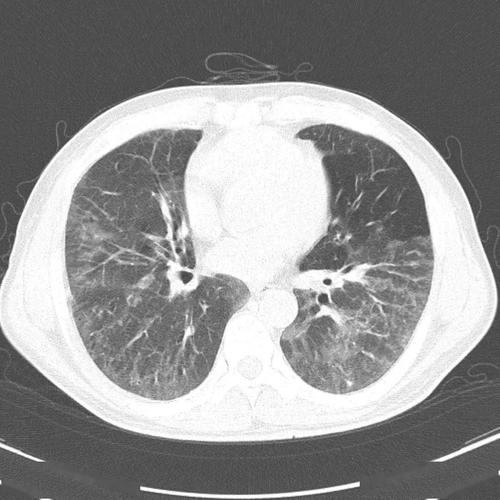

间质性肺炎的典型图谱,最全解析!

极易漏诊的间质性肺炎,从ct上怎么看?

间质性肺炎ct表现

间质性肺炎ct

间质性肺炎ct图片

间质性肺炎早期ct图片